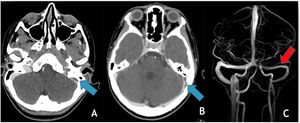

There were two additional cases where no etiological cause was found: one case of right thalamic venous stroke with thrombosis of the straight sinus, galen and cerebral veins and one newborn with left transverse sinus and cortical veins thrombosis (Fig. 3), with a perinatal history of a cesarean section birth with ventouse, for stationary labor.

(A) Axial depicts SWI, hypointensity (“blooming effect”) along a cortical vein located in the high convexity (green arrow) indicating the presence of thrombus and sub-arachnoid hemorrhage (blue arrows); (B) axial T1WI reveals spontaneous hyperintensity in a cortical vein located in the high convexity on the right – endoluminal thrombus; (C) MRV (3D reconstruction), poor visualization of the cortical veins draining into the superior sagittal sinus, which is itself patent.